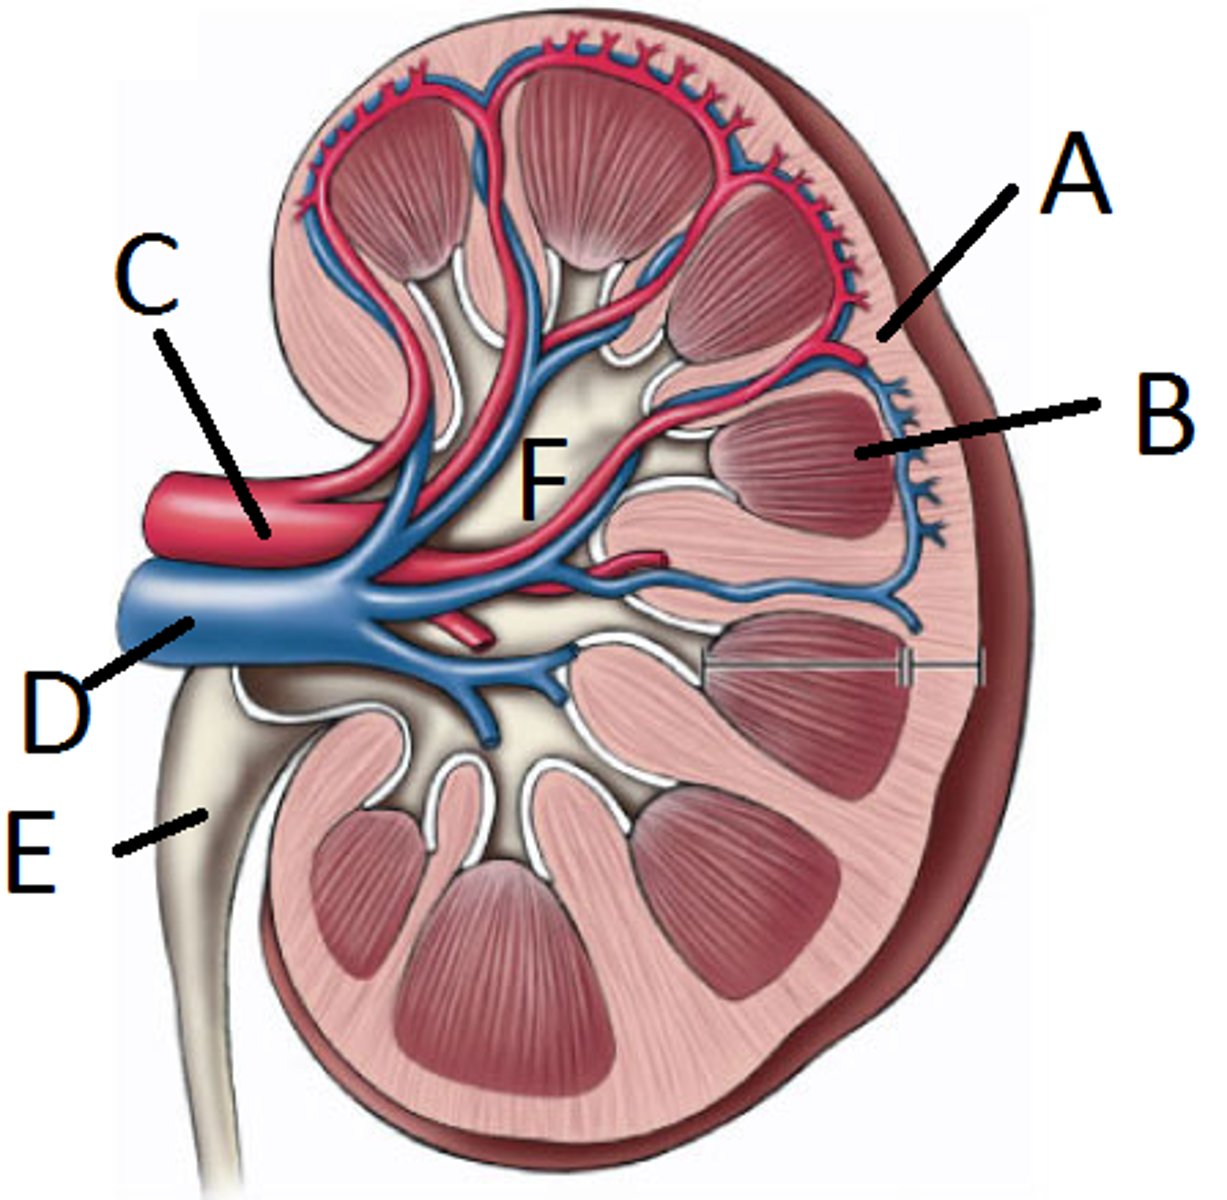

renal artery

C

renal vein

D

segmental

both vessels

interlobar

both vessels

interlobular

both vessels

arcuate

both vessels

E